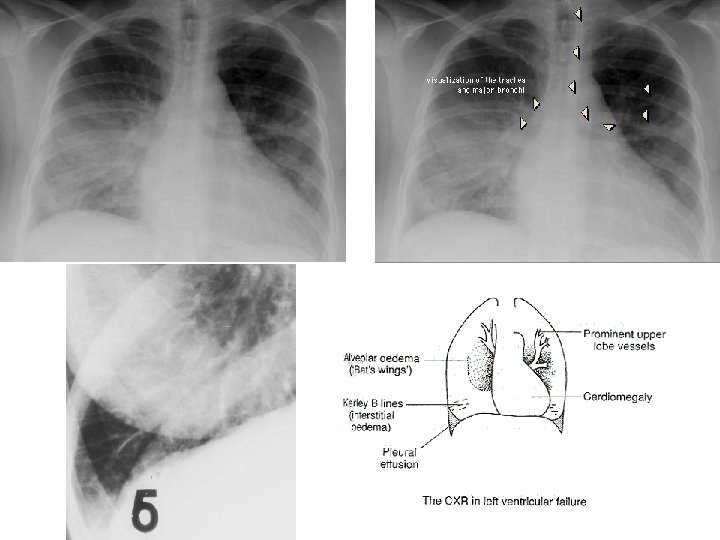

CONGESTION • LUNG – ACUTE – CHRONIC • LIVER – ACUTE – CHRONIC • CEREBRAL

ACUTE PASSIVE HYPEREMIA/CONGESTION, LUNG

Kerley B Air Bronchogram

CHRONIC PASSIVE HYPEREMIA/CONGESTION, LUNG